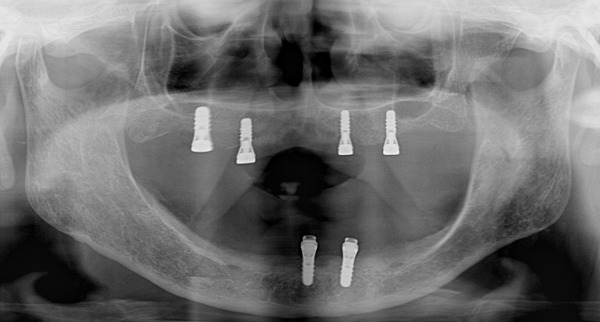

こちらはレントゲン写真になります。

歯がある正常な方と比較すると下顎の骨が非常に細く吸収してしまっているのが分かるかと思います。

上下インプラントが入った状態のレントゲン写真になります。

初診でレントゲン写真を見たとき正直、骨も少なく、年齢や持病など全身的なことからインプラント治療をお断りしようかと思いました。